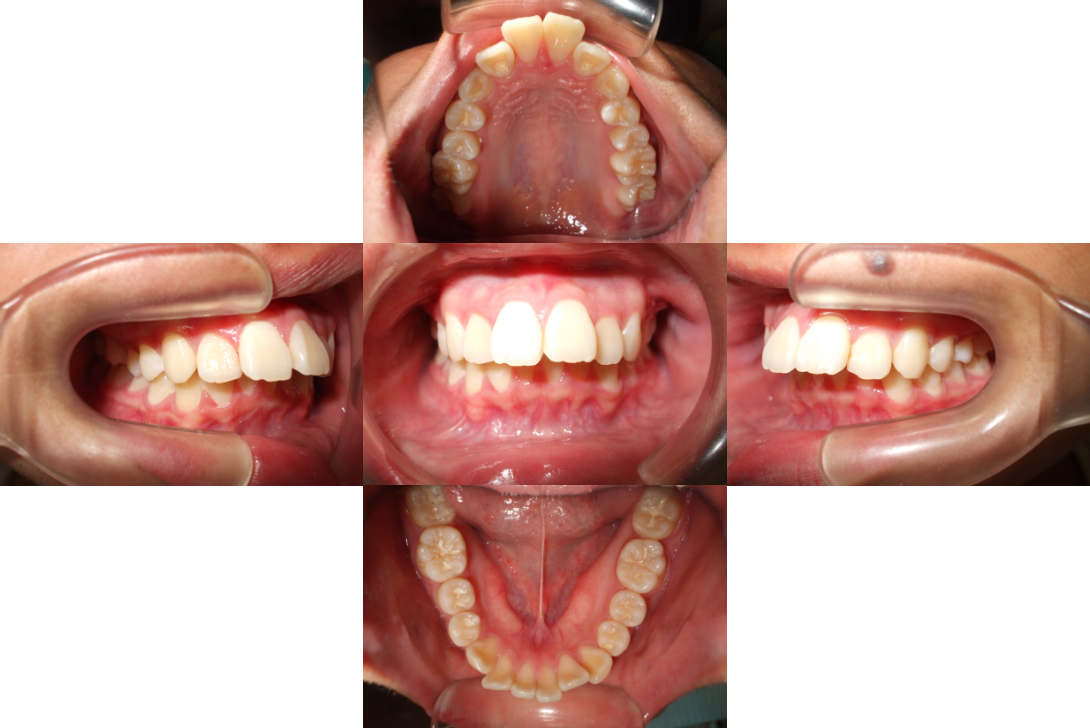

過蓋咬合を抜歯とDBSで改善した症例

※DBSとはダイレクトボンディングシステムと呼ばれており、ブラケットにワイヤーを通して歯を動かしていく矯正治療です。

患者情報

16歳女性

主訴

前歯がでてる

行った治療内容

上顎両側4番抜歯、DBS

治療のリスク

歯根吸収、前歯部歯肉退縮

治療期間

動的治療期間4年0か月

※ クリックして拡大することができます。